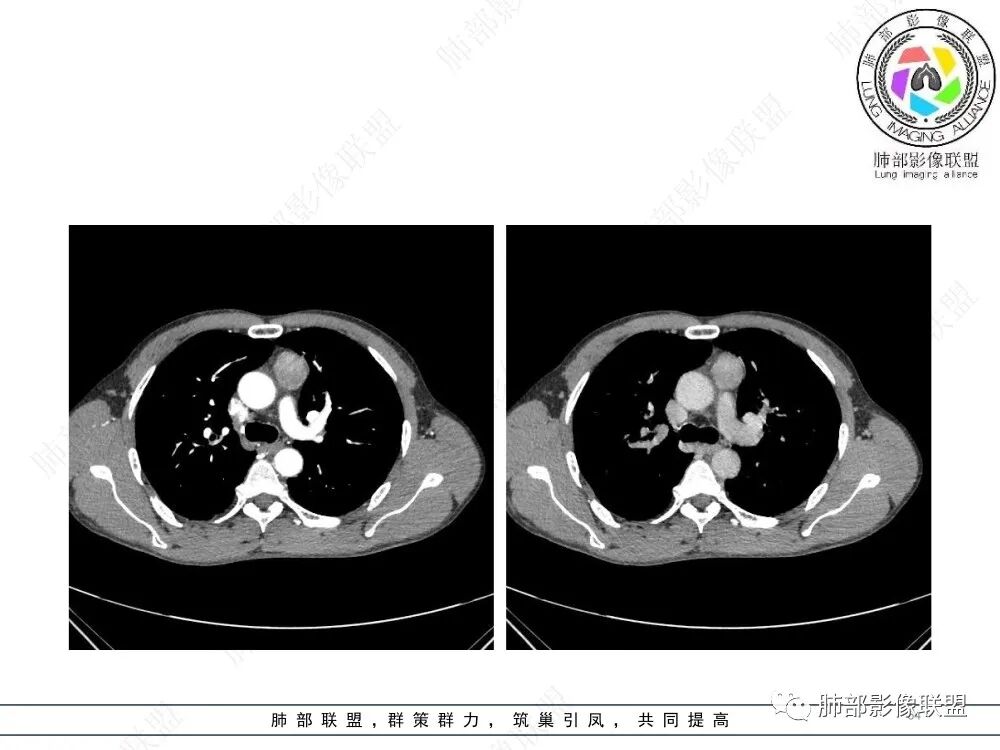

2、影像特点:前纵隔偏左侧软组织影,密度相对均匀,未见明显包膜钙化及实质内钙化,局部边缘浅分叶,周围脂肪间隙密度增高、浑浊,未见侵犯大血管、未见纵隔内淋巴结转移、未见侵犯心包内结构、未见胸膜转移结节、未见肿块沿着纵隔胸膜蔓延,未见胸腔积液。增强后动脉期不均匀强化,未见明显纤维分隔。

3、 病 例 小 结:40岁以上,前纵隔偏侧性生长的肿块,常规考虑胸腺瘤。难点就在于胸腺瘤的分型。但是对于前纵隔占位影像诊断的关键在于区分胸腺囊肿、胸腺瘤、胸腺癌及其他恶性肿瘤。至于胸腺瘤,主要在于判断有无侵袭性。

衡妈🇨🇳:中年男性,前纵隔偏左侧实性占位,密度相对均匀,边缘分叶,周围脂肪结构略模糊,增强后动脉期不均匀强化,有低密度区,纤维分隔显示不清。考虑胸腺瘤B1 B2型。

谢加平:前纵隔左侧肿块,边界清,强化较均匀,内侧有侵犯脂肪间隙,恶性特点,选胸腺瘤。